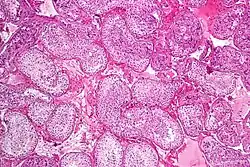

![]() Seminiferous tubule with maturing sperm. H&E stain. | |